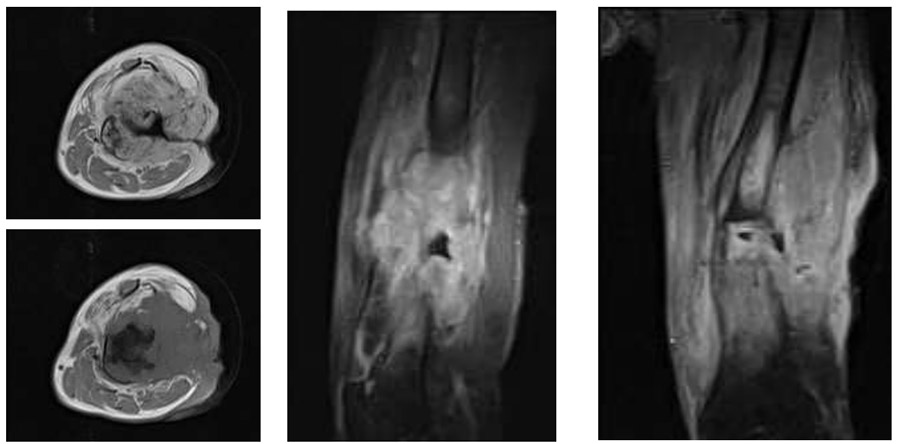

Ameliyat Öncesi: MR’da ciddi kemik harabiyetine neden olan cildi invaze eden düzensiz sınırlı heterojen kitle görülmekte